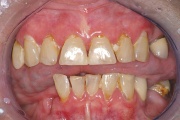

Sjögreni sündroomi võimalusele mõeldakse silmade ja suu kuivuse all kannatavatel patsientidel. Süsteemne haigus, mida iseloomustab kõigi eksokriinsete näärmete talitluse puudulikkus kroonilise põletikulise destruktsiooni tõttu. Keratokonjunktiviit Kserostoomia Polüartriit Loe edasi »